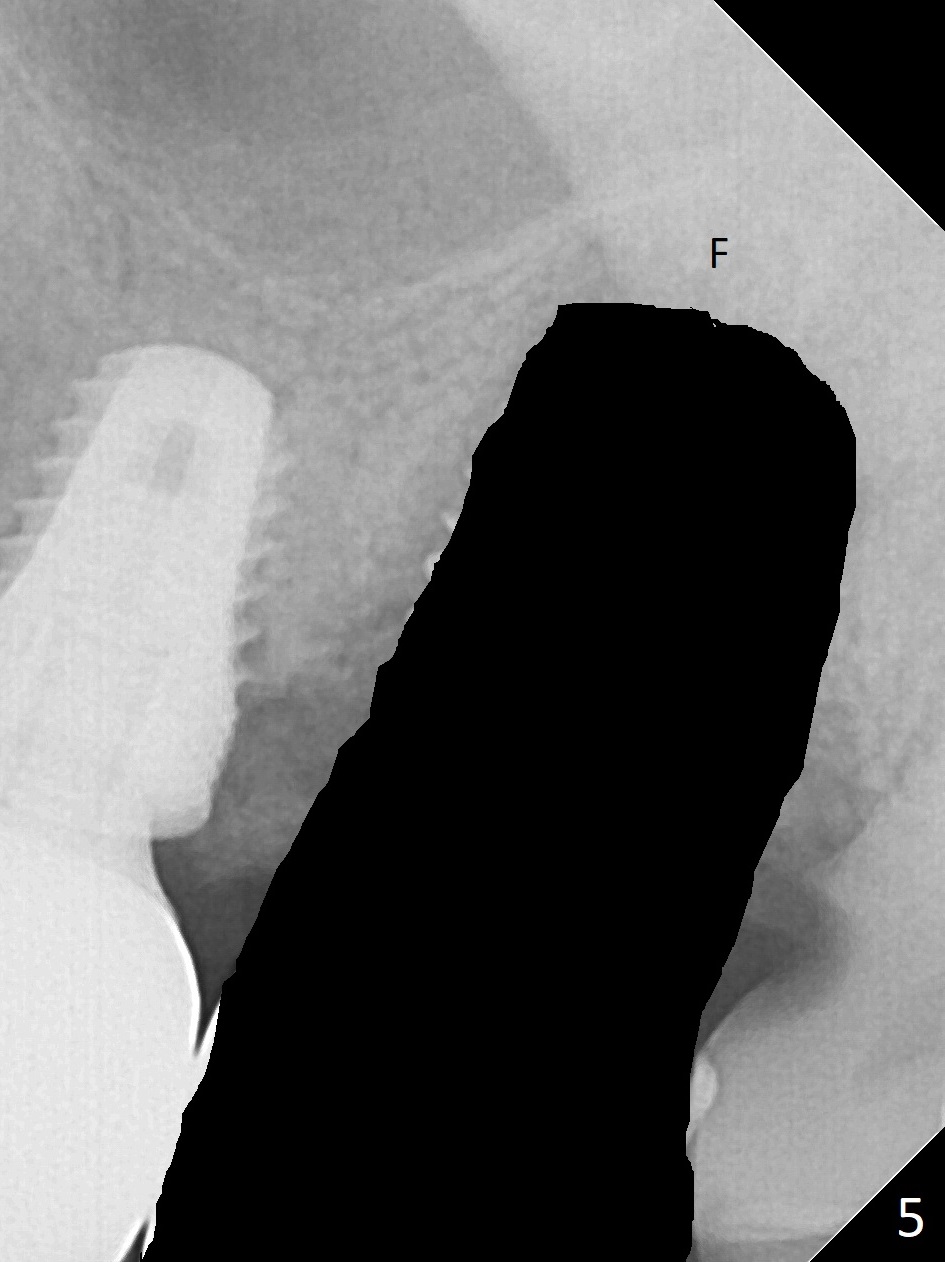

The 7x14 mm implant at #15 of a 89-year-old man is found to be loose ~ 1 year post cementation (Fig.1). After implant removal and debridement, bone graft is placed (Fig.2 G); the mesiocervical caries of the 3rd molar is removed, but not filled (*). With collagen membrane fixed with Chromic gut suture (Fig.3), setting acrylic is applied in the edentulous area, including the mesiocervical cavitation of the 3rd molar (Fig.4) for further retention. Bone graft gets lost following socket preservation at #31 with periodontal dressing. When the bone graft matures, a new implant (Fig.6 green) will get primary stability from the native bone, i.e., coronal to the sinus floor (Fig.5 F). The acrylic dressing (Fig.7 A) with a portion locking to the undercut of the neighboring crown (*) remains in place 5 weeks postop. When the dressing is cut off, the bone graft is exposed with odor (Fig.8,9 *). Periodontal dressing is applied. The distolingual portion of it gets lost due to brushing a day later. When he returns, the dressing is removed (Fig.10). It appears that the growing in gingival margin is pushing the bone graft out. A moment later after just a few rounds of swallowing, more graft is lost (Fig.11). We would love to leave the wound open, but the senior citizen complains of air leaking and requests reapplication of periodontal dressing. The bone graft is almost gone when the 2nd periodontal dressing is removed nearly 2 months postop (Fig.12). The tooth sensitivity disappears when MO caries is taken care of. The socket has a dimple 5 months postop (Fig.13), although it is filled with bone graft (Fig.14). Due to low bone density (~500 HU), sinus lift is required for implant stability with PRF (Fig.15). In fact the lab chooses not to do sinus lift.